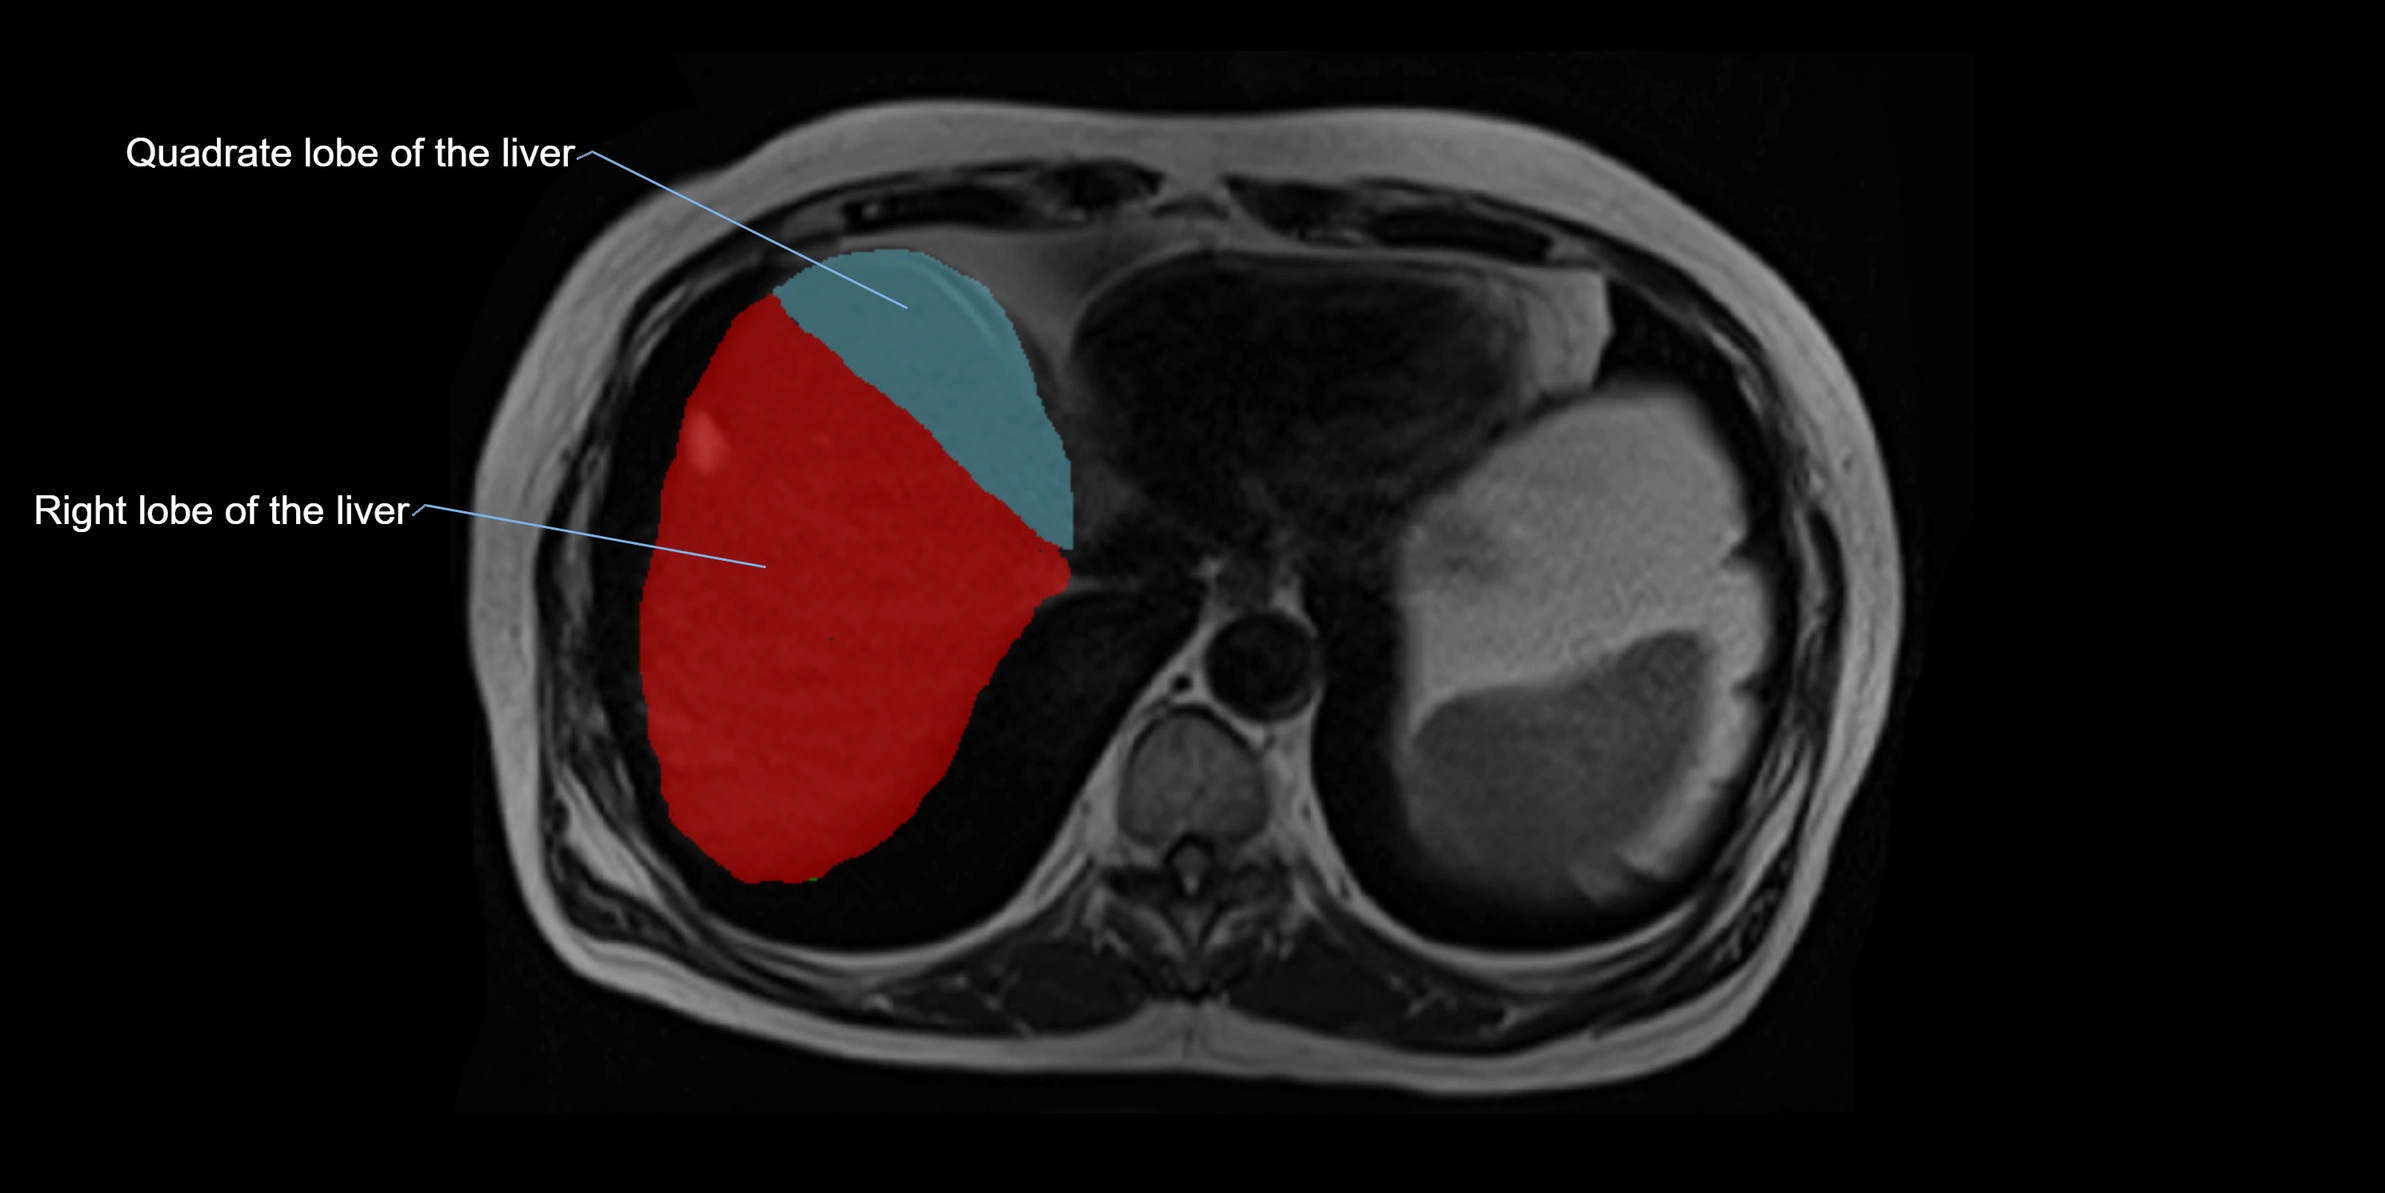

The caudate lobe of the liver is a distinct anatomical subdivision of the liver, designated as segment I in Couinaud’s classification. It lies on the posterior surface of the liver, between the fissure for the ligamentum venosum (left boundary) and the groove for the inferior vena cava (IVC) (right boundary). Superiorly, it is related to the posterior liver surface, and inferiorly it is separated from the left lobe by the porta hepatis.

This anatomical autonomy makes the caudate lobe especially significant in liver surgery, transplantation, and hepatic venous outflow obstruction syndromes (e.g., Budd–Chiari syndrome). Enlargement of the caudate lobe is a characteristic imaging feature in chronic liver disease and cirrhosis.

• Enlargement may be appreciated in cirrhosis or Budd–Chiari syndrome